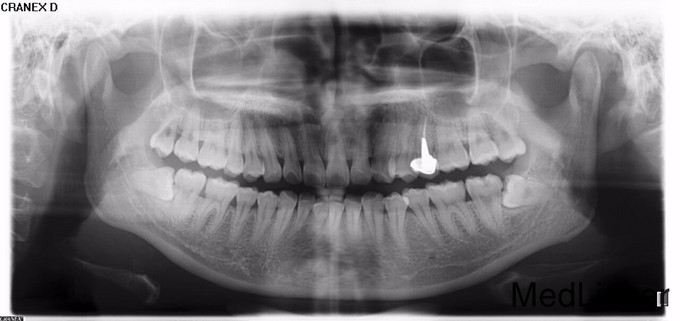

1113水平阻生智齿的拔除光26

两侧下后牙塞食物,要求拔牙

水平阻生智齿拔除